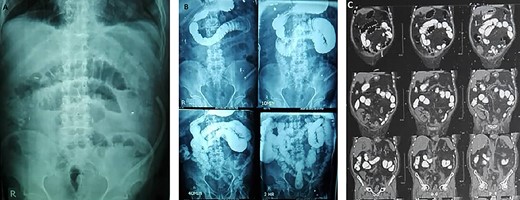

Midline incision was made and we tried to enter the Retzius space by focusing the dissection on the opposite side of the transplanted kidney. The bladder became separated from the scar tissue on the side of the graft by identifying the Cooper’s ligament as a landmark. The peritoneum was incised, and after bowel mobilization, bilateral native ureters were dissected free from their attachment and were ligated by silk 2/0 sutures. Blunt dissection was avoided in the right side to prevent injury to the graft ureter (Fig. 2). The distal ureteral margins were free of tumor in the frozen section analysis. RC was performed and maximum length of the graft ureter was preserved. Extended PLND on left side and limited PLND on right side were performed. The patient underwent ileal orthotopic neobladder reconstruction, and the graft ureter was reimplanted to ascending loop of the pouch with end-to-end anastomosis (Fig. 3).

The graft ureter was reimplanted to the ascending loop of the pouch with end-to-end anastomosis.